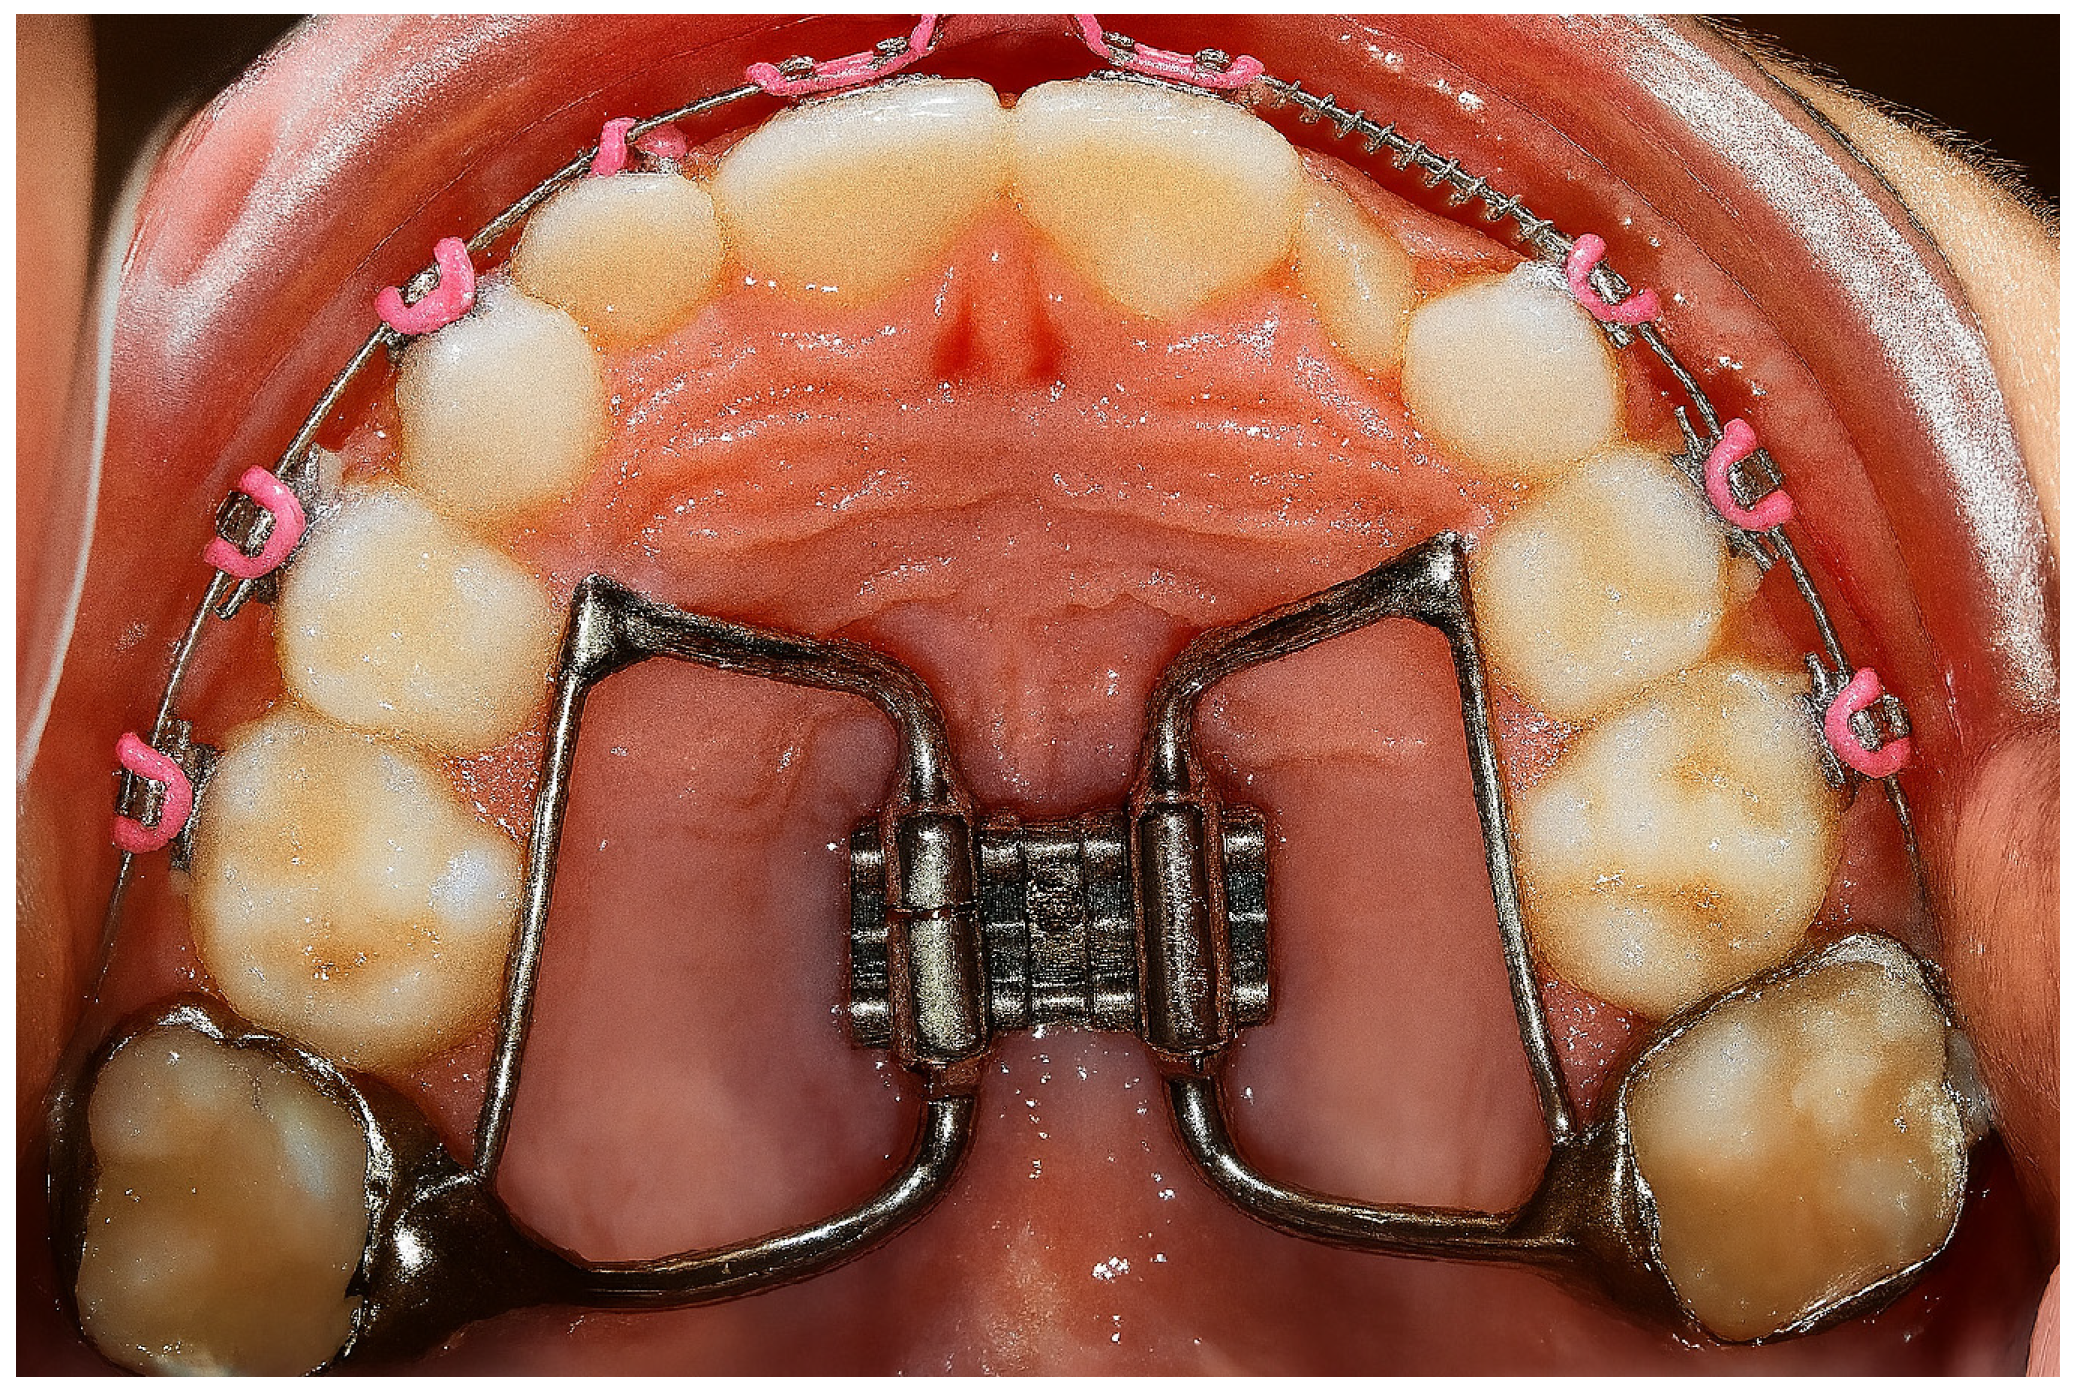

| Intervention (I) | Treatment with rapid maxillary expansion (RME) using orthopedic or orthodontic appliances (e.g., Hyrax, Haas, bonded or banded expanders), activated at rates ranging from 0.25 to 0.5 mm per day. Diagnosis was confirmed through polysomnography (PSG) or based on clinical and symptomatic evaluation in combination with instrumental assessments such as CBCT, lateral cephalograms, and rhinomanometry. |